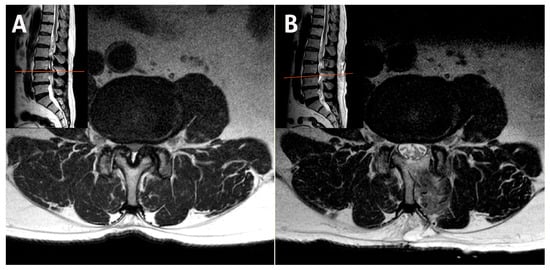

2.2. Case 2: Bilateral–Contralateral Decompression in Adjacent Segmental Stenosis (ASS) After Lumbar Fusion

| 2 | 82 | F | Adjacent Segment Stenosis | L2–L3 | 68 | 7 | 3 | 8 | 3 | 58 | 26 | None | 6 |